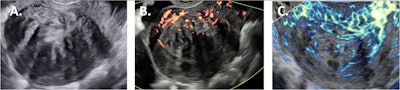

Sagittal fibroid images obtained by the different ultrasound techniques. 2D B-mode ultrasound (A); 2D power Doppler (B); 2D microvascular flow (C).All images courtesy of Derk Jan Slotman et al and Insights Into Imaging. Available for republishing under Creative Commons license (CC BY-NC-ND 4.0).

In the article, they discuss the range of ultrasound methods, including the different Doppler techniques used for perfusion imaging. Microvascular flow (MV) and contrast-enhanced ultrasound imaging can be used for blood flow in smaller blood vessels, according to the authors, who describe the benefits and limitations of each method.